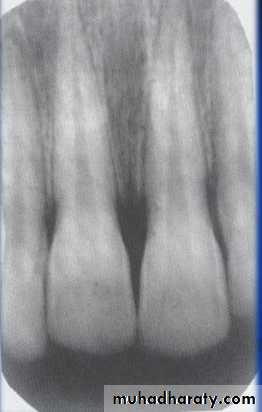

Examination of bone:Height of alveolar bone

Crest relative to teeth

Loss of height-more than 1.5 mm periodontal disease

Lamina dura + PDL space + tooth roots